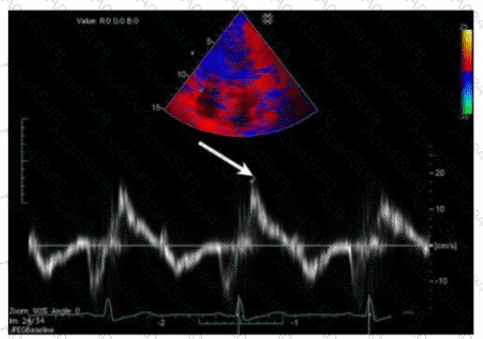

Which measurement is indicated by the arrow on this image?

The Doppler tissue imaging waveform shown indicates the systolic annular velocity of the tricuspid valve annulus, labeled as S’. This measurement reflects right ventricular systolic function by quantifying the velocity of longitudinal myocardial motion during systole.

The a’ wave corresponds to atrial contraction, not systole. S’ assesses systolic function, whereas e’ and a’ relate to diastolic phases.